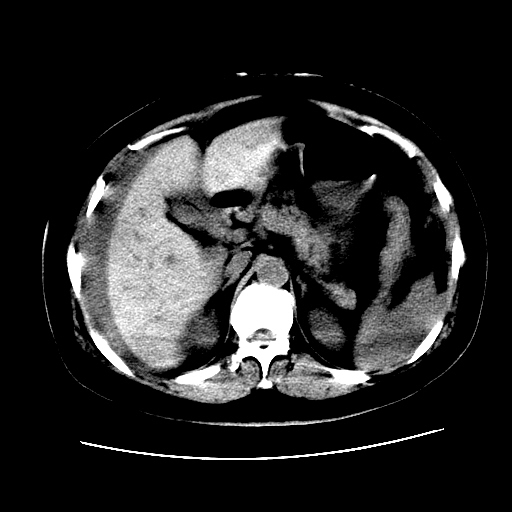

f,45y.怀孕4月晕倒,b超提示死胎,有手术结果,请展开讨论后明天告诉。

膈下-肠间隙内见气体密度影,子宫轮廓显示不清,宫腔-腹腔积液,首选考虑---子宫破裂出血。

1)宫腔妊娠。2)子宫破裂出血,腹腔及盆腔积血。

盆腔积液考虑破裂,至于说那裂了,那要不是宫外孕就是子宫破了要是宫外动就是宫外孕破裂出血

正常怀孕什么样从没在ct上看过,所以不知道位置是什么样的,我考虑宫外孕

感谢同行们的高见。手术结果:子宫破裂出血。

我们的诊断是:腹、盆腔积液(考虑腹盆腔脏器破裂出血);宫腔妊娠。让人纳闷的是当时我们没有经验,现在回头看看分析:4月宫腔妊娠:1、洋膜囊不可能紧贴胎体这么小;2仔细看看子宫后壁肌层模糊不清;3腹、盆腔液体来源原因?4、45岁高龄妊娠有晕倒。由此可大胆诊断:宫腔妊娠子宫破裂出血。